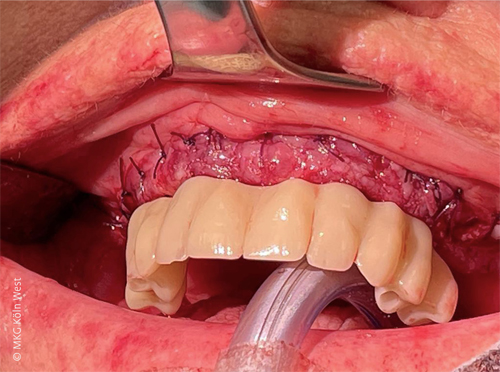

Direkt im Anschluss an die Implantation wurde durch die prothetische Überweiserin eine provisorische Brücke auf dem Implantatgerüst verschraubt, sodass die Patientin bereits beim Erwachen aus der Narkose mit festsitzenden Zähnen versorgt war.

Der postoperative Verlauf war komplikationslos; insbesondere traten keine Wundheilungsstörungen oder Infektionen auf. Nach einer Einheilphase von etwa acht Wochen erhielt die Patientin ihre definitive prothetische Versorgung in Form einer auf den vier Pfeilern verschraubten Stegprothese.

Intraoperativ konnte auf den sechs Pfeilern eine provisorische Interimsbrücke verschraubt werden, die eine sofortige provisorische Versorgung gewährleistete. Nach komplikationsfreier Wundheilung erhielt die Patientin acht Wochen postoperativ die definitive festsitzende Brückenversorgung im Oberkiefer.